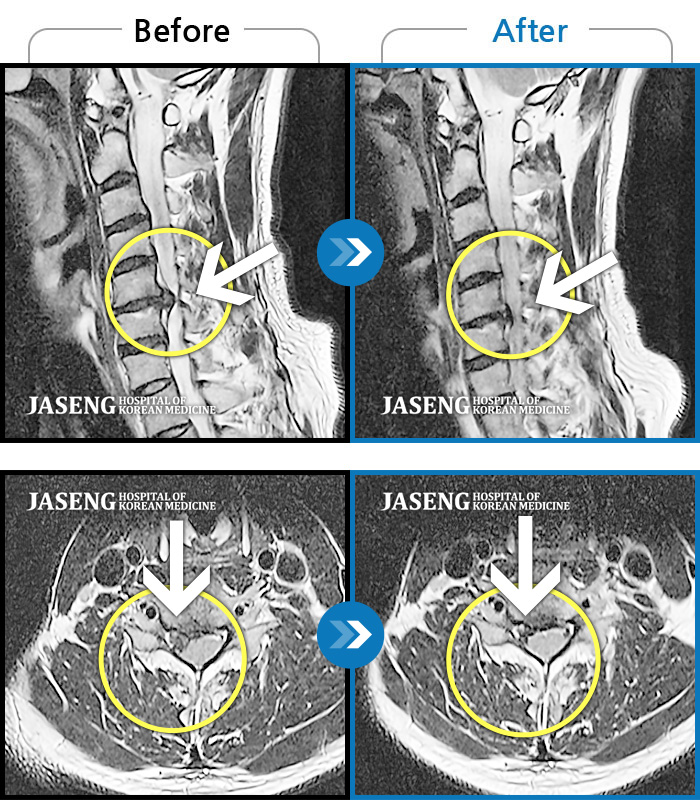

Before

After

환자에게 사전 동의를 받아 동일 조건에서 촬영되었습니다.

개인에 따라 치료 후 부작용이 발생할 수 있으니 의료진과 상담 후 치료를 진행하시기 바랍니다.

좌측 허리 골반 및 하지 방사통, 야간통

허리 골반 통증, 왼쪽 허벅지에서 종아리 발까지 당김 증세 및 통증